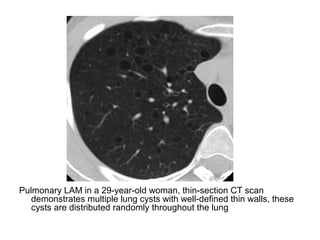

Pulmonary LAM in a 29-year-old woman, thin-section CT scan

demonstrates multiple lung cysts with well-defined thin walls, these

cysts are distributed randomly throughout the lung